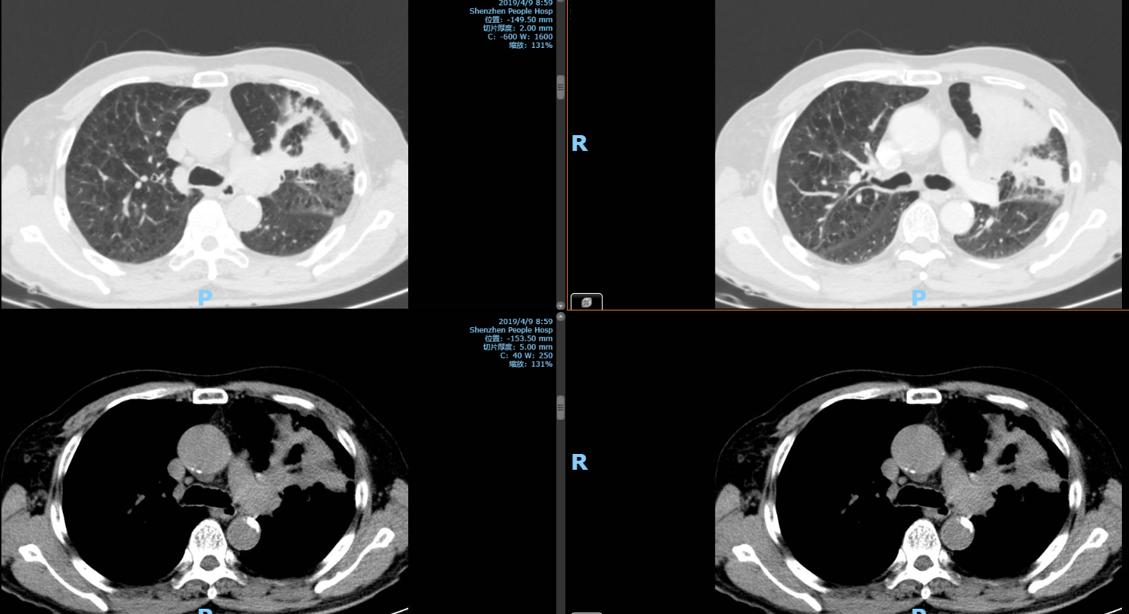

2019-04-09胸腹部增强CT:左肺上叶-左肺门可见大片不规则实变影较前明显并中度强化,左肺上叶支气管变窄,左肺门及纵膈可见数枚小淋巴结,需考虑肿瘤性病变,两肺慢性支气管炎、肺气肿。

支气管活检病理:(左上叶新生物)小活检标本,结合免疫组化结果,病变为肺浸润性鳞状细胞癌。IHC:P40(+)、P63(+)、NapsinA(-)、TTF-1(-)。